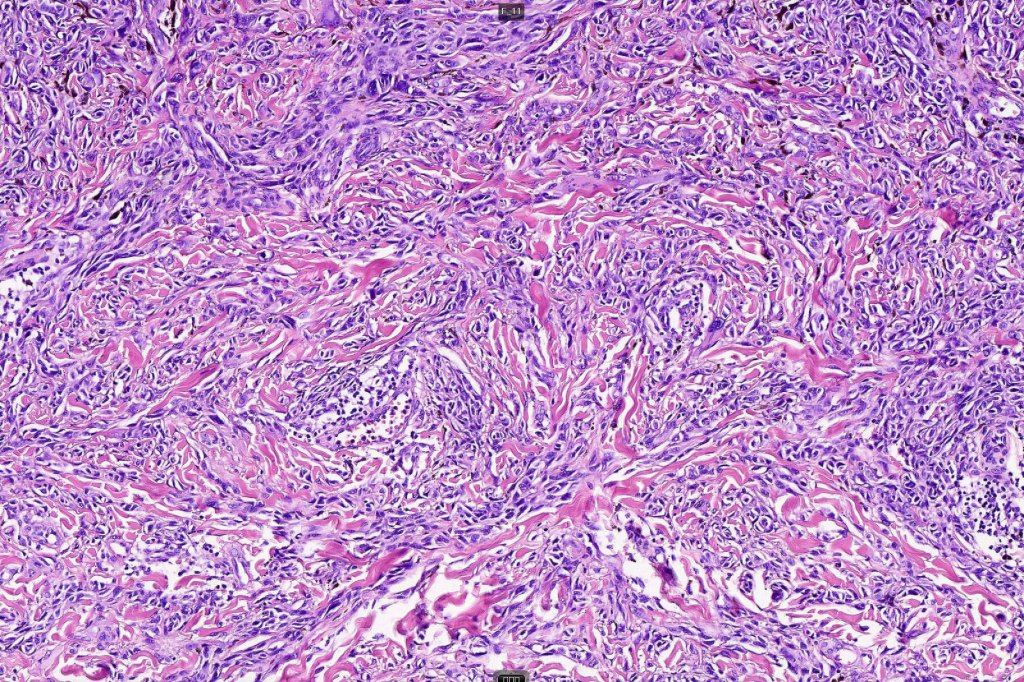

•Sharply circumscribed (begins and ends with a nest), symmetrical dome-shaped lesion. Symmetry is both horizontal and vertical (see image below)

•Wedge-shaped with the base uppermost or sometimes plaque-shaped silhouette

•Matures with depth-often best recognized at scanning/low power magnification & readily confirmed with S100 or MART1

•Maturation implies nest size and cell size diminishing with depth, at the base, the infiltrate may have a single cell infiltrating pattern